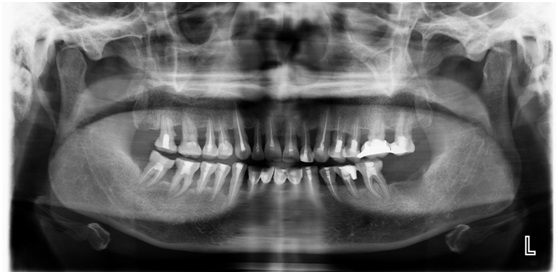

接着全口牙齿行翻瓣术,全口牙齿行松牙固定术,双侧后牙牙冠行固定桥修复。

固定桥修复后照片: